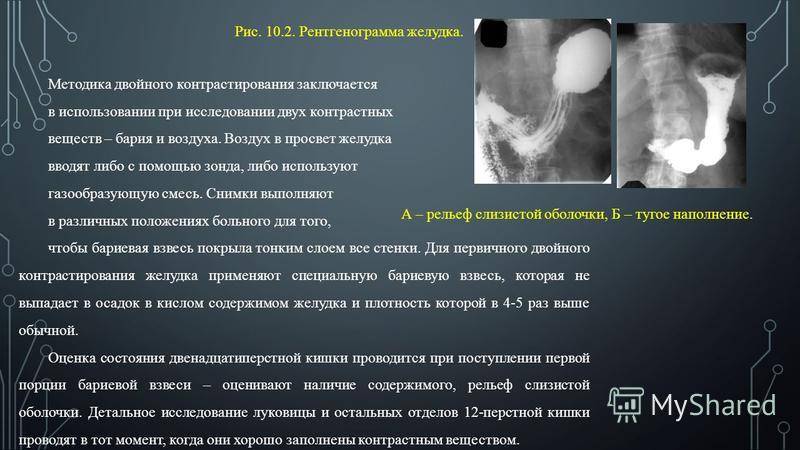

Современные технологии в медицине: рентгенодиагностика заболеваний желудка

Раздел: Фотогалерея мыслей